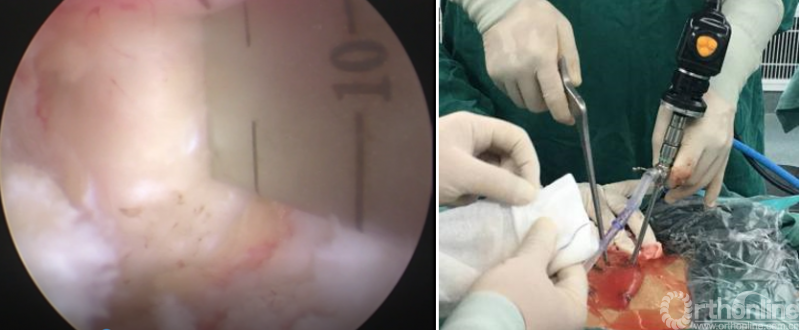

第二步“剥”:剥离器+射频剥离、止血、造腔,显露下关节突尖部;

第三步“凿”:凿除部分下关节突;

第四步“分”:分离上关节突及黄韧带;

第五步“咬”:咬除部分上关节突,显露椎间盘及神经根;

第六步“切”:切除椎间盘;

第七步“牵”:神经拉钩牵拉保护神经根;

第八步“铰”:铰刀置入处理上下终板(刮勺置入处理终板);